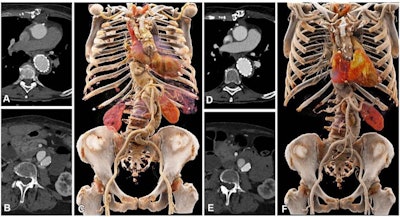

Comparison of image quality between EID CT with standard contrast media protocol and PCD CT with low-volume contrast media protocol using a matched radiation dose. Transverse and three-dimensional cinematic rendered images from thoracoabdominal CTA in a 71-year-old woman in group 2 are shown. (A-C) Images from third-generation EID CT with automated tube voltage selection of 90 kVp. BMI, effective diameter, CTDIvol, and SSDE were 23.7 kg/m2, 278 mm, 3.98 mGy, and 5.25 mGy, respectively; 70 mL of contrast media was used. (D-F) Images from PCD CT with reduced contrast media volume of 52.5 mL and VMI at 50 keV. Time interval between scans was 6 months. Mean BMI, effective diameter, CTDIvol, and SSDE at the time of the second scan were 24.2 kg/m2, 282 mm, 3.99 mGy, and 5.27 mGy, respectively. Mean contrast-to-noise ratio for EID CT and PCD CT were 17.2 and 17.9, respectively. BMI = body mass index, CTA = CT angiography, CTDIvol = volumetric CT dose index, EID = energy-integrating detector, PCD = photon-counting detector, SSDE = size-specific dose estimate, VMI = virtual monoenergetic images. Images and caption courtesy of the Radiological Society of North America.First author Dr. Kai Higashigaito, also of the University Hospital Zurich, and colleagues conducted a study that explored use of a low-volume contrast media protocol with PCCT for CCTA of the aorta in the chest and abdomen. The research included 100 people, all of whom had undergone CCTA with conventional CT and all of whom underwent CCTA with PCCT. The study participants were divided into two groups: 40 people who underwent imaging between April and May 2021, and 60 who underwent imaging between June and September 2021.

Among the first group, the team found that PCCT conducted at 50 keV offered "the best trade-off between objective and subjective image quality," reaching a 25% higher contrast-to-noise ratio compared with conventional CT. In the second group, contrast media volume was reduced by 25%.